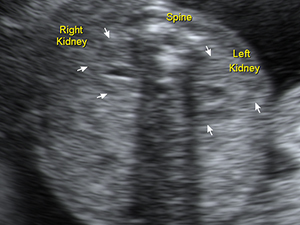

脊椎

中孕期的胎兒脊骨

腹部

兩個胎兒腎臟